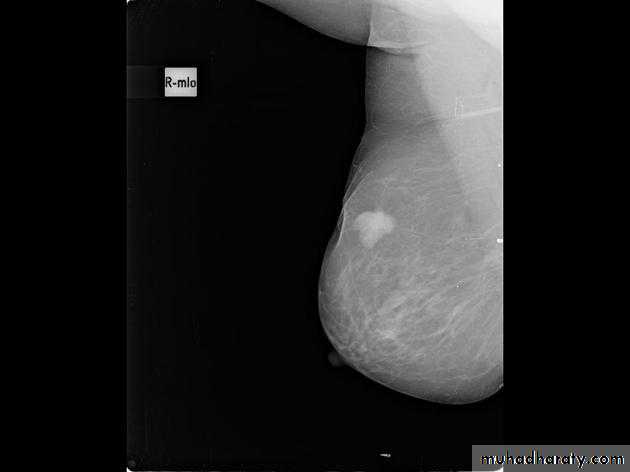

The mediolateral oblique (MLO) view is one of standard mammographic views. It is the most important projection as it allows to depict most breast tissue.The craniocaudal view (CC view), is one of the two standard projections in a screening mammography. It must show the medial part as well the external lateral portion of the breast as much as possible.